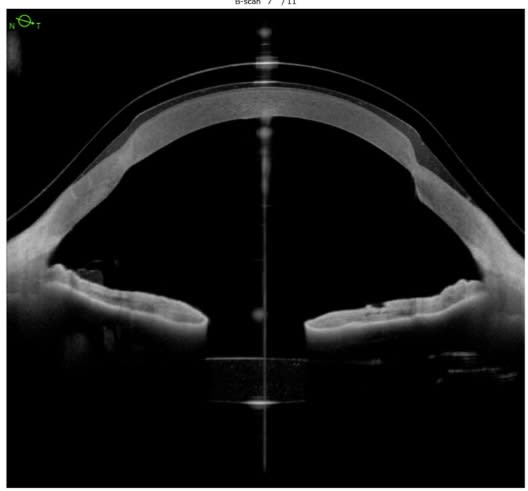

A well-fitting scleral contact lens will clear the cornea and limbus by precise amounts, and land evenly on the sclera. Anterior-segment (AS)-OCT gives precise views of central and limbal clearance. Aligning a scleral lens chamber to the peri-limbal area can be a challenging part of a fitting, especially in eyes that are significantly irregular in shape due to their post-surgical status. An example: Those that have undergone radial keratotomy or corneal transplantation. An AS-OCT can assist in modifications that are difficult to assess in the slit lamp.